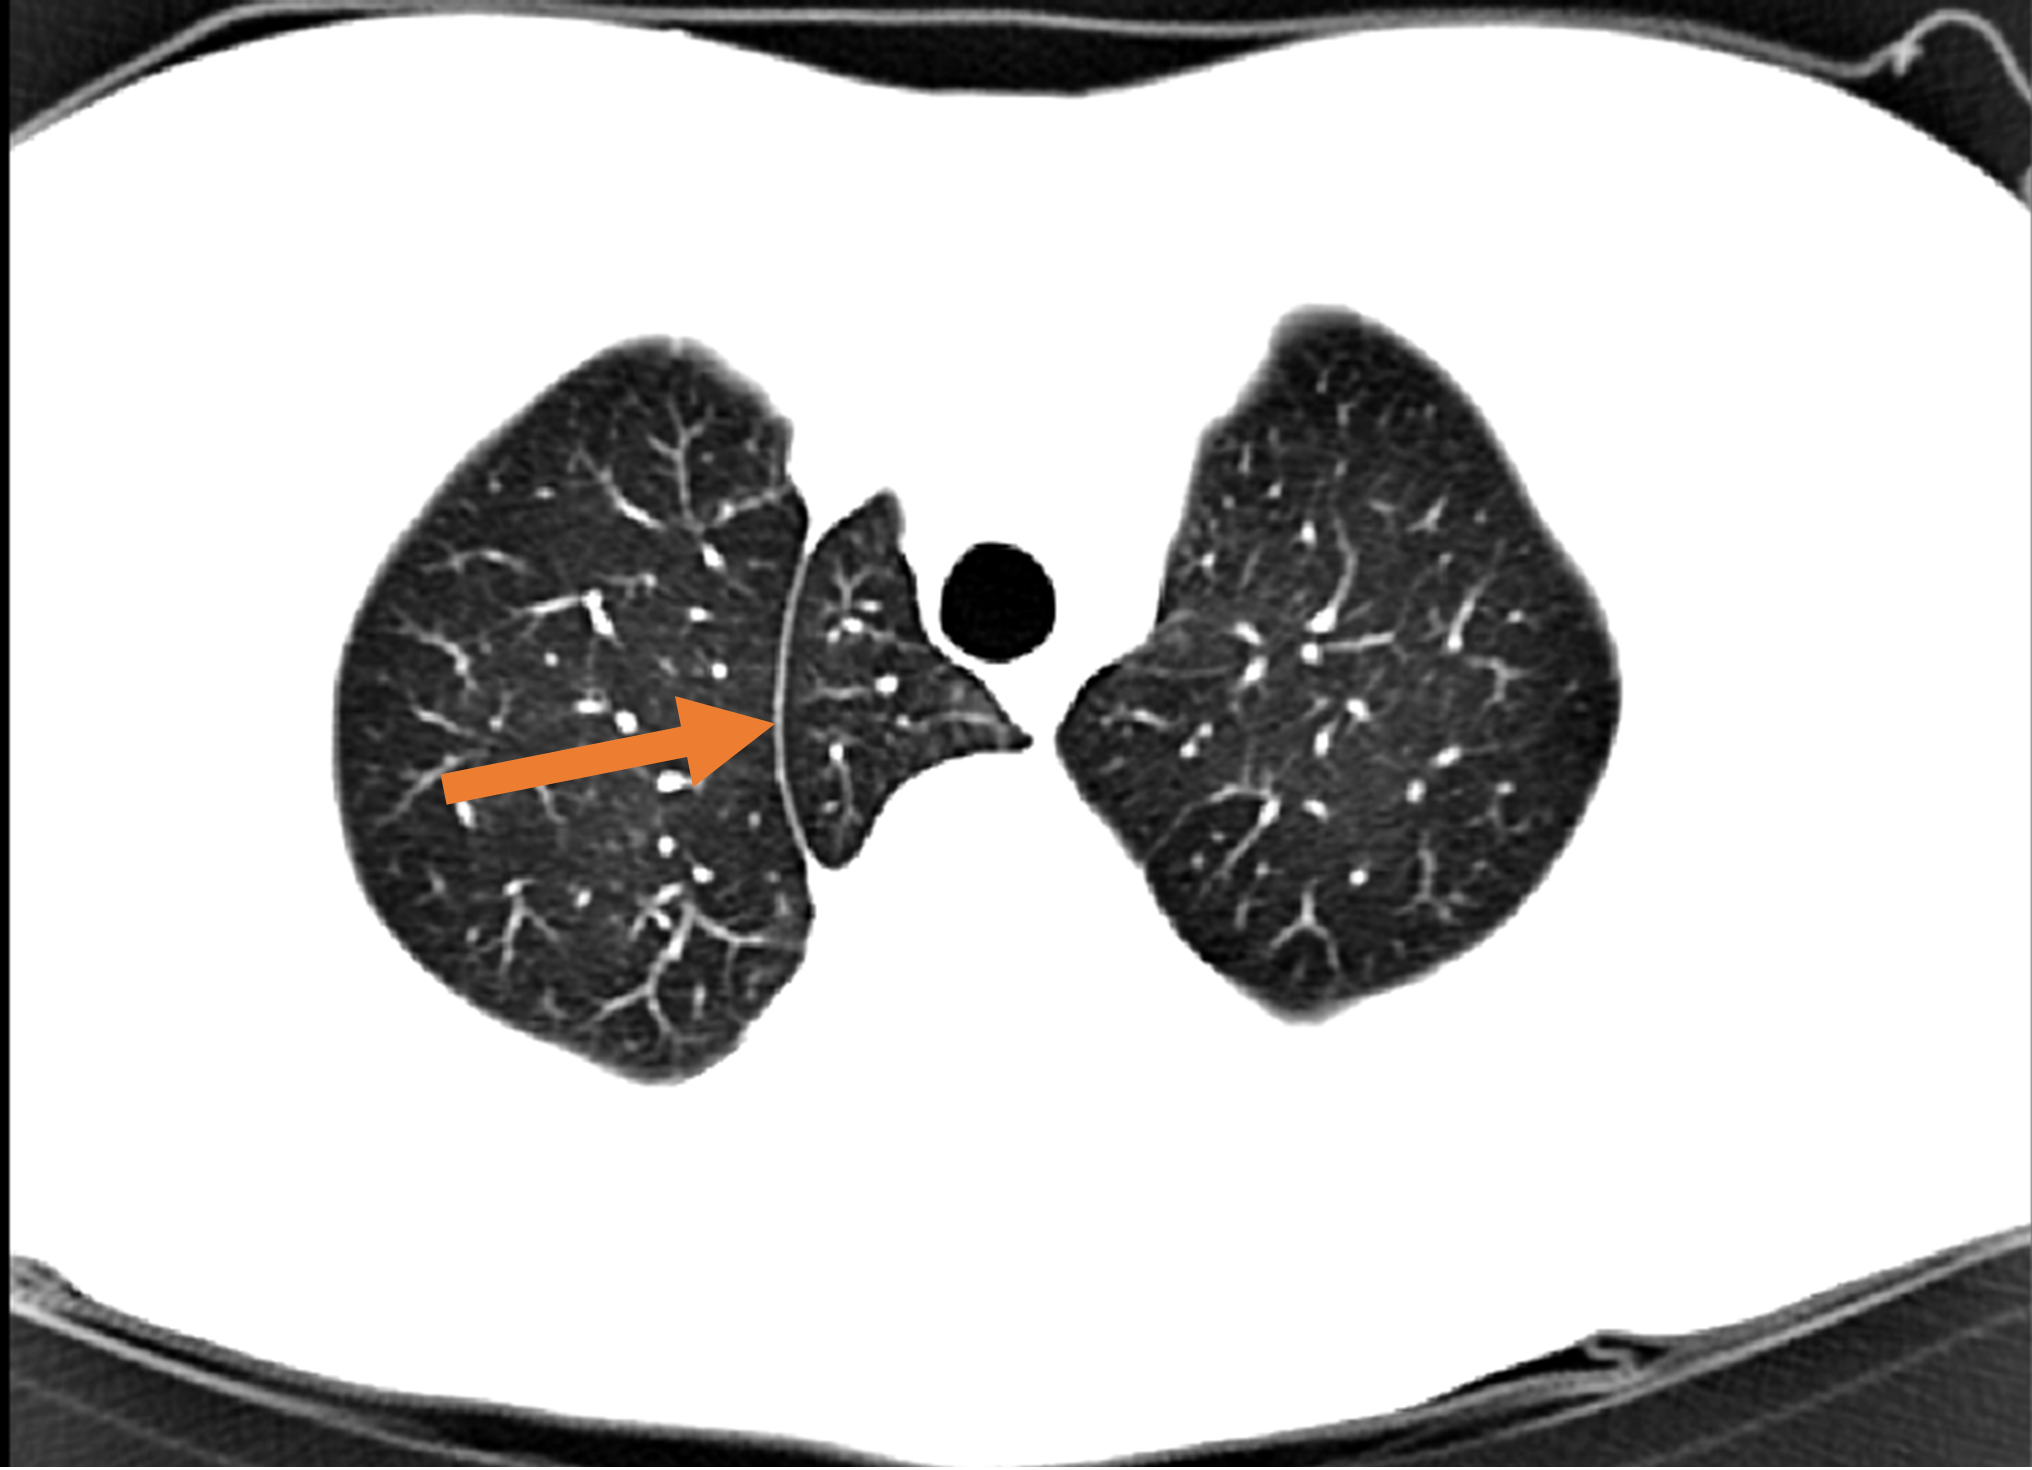

Edge-Aware 3D Image Segmentation Networks

[91]: Automated segmentation of kidneys and kidney tumors is an important step in quantifying the tumor’s morphometrical details to monitor the progression of the disease and accurately compare decisions regarding the kidney tumor treatment. Manual delineation techniques are often tedious, error-prone and require expert knowledge for creating unambiguous representation of kidneys and kidney tumors segmentation. We propose a 3D end-to-end edge-aware FCN for reliable kidney and kidney tumor semantic segmentation from arterial phase abdominal 3D CT scans. Our segmentation network consists of an encoder-decoder architecture that specifically accounts for organ and tumor semantics. We evaluate our model on the 2019 MICCAI KiTS Kidney Tumor Segmentation Challenge dataset. -